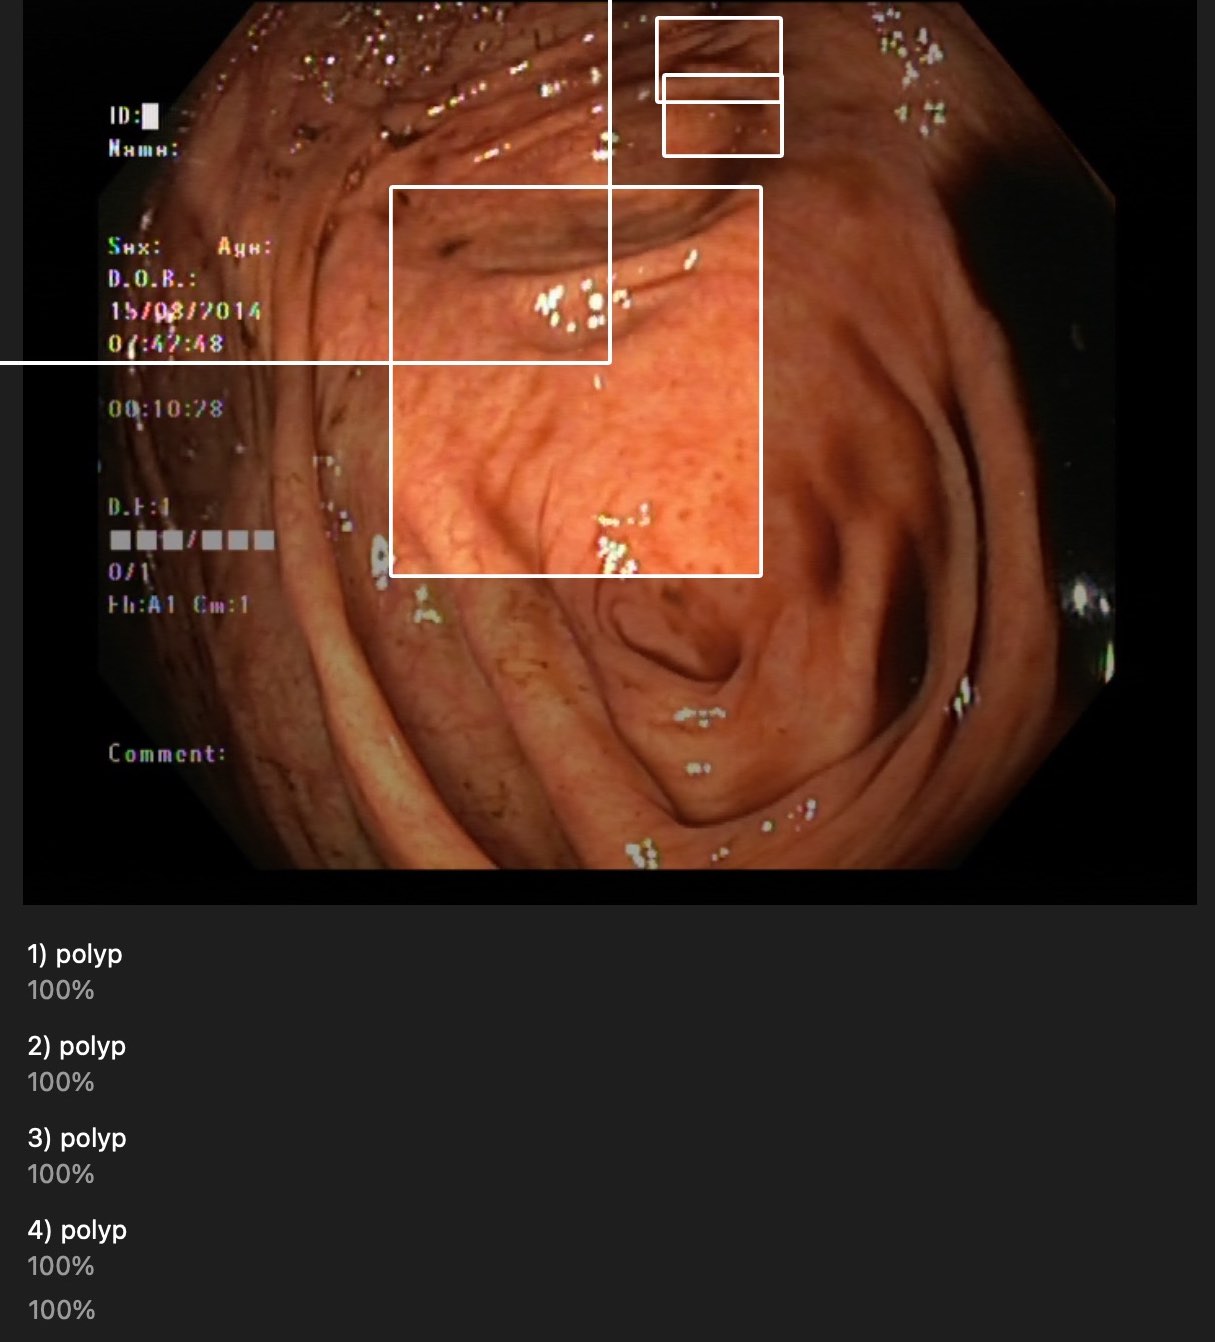

They are near polyps but most of them are not surrounding correctly.